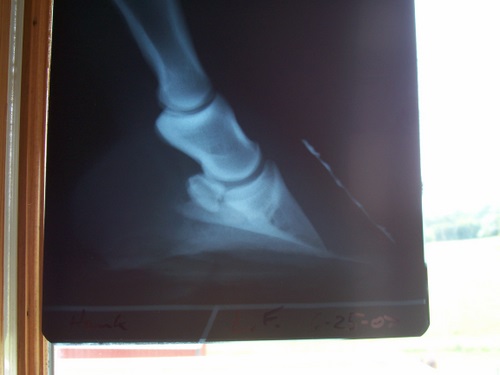

Posted on Monday, Jul 9, 2007 - 2:29 pm: Dr.O I went and got Hanks X-rays and would appreciate any input you have. I have to do something soon with his hooves and I haven't heard anything from the 2 farriers that have dealt with this. I may have to go with my regular inexperienced farrier, so any input will be greatly appreciated!As I said before not the greatest x-rays, but it's all I have. I think the left front got taken at an angle, I can't remember what the vet said how it happened. I think the block turned a little if I recall. Left front Right front

Posted on Monday, Jul 9, 2007 - 7:10 pm: Oh Diane, I'm anxious to hear what Dr. O says, but from the radiographs, I'd say he really needs a farrier experienced with rotated horses and theraputic trimming/shoeing. I'm sorry you haven't heard back from your prospects! Only four weeks? Those toes are really long. I think if his breakover could be brought back to the proper alignment with the tip of the coffin bone, possibly removing some underrun heel and a natural balance shoe PROPERLY placed (perhaps with a wedge pad after the removal of some heel) the alignment would look better and you'd have a start on derotation. It's hard to tell from the radiographs how far the tip of his coffin bone is from the surface, and that's an important piece of info. The NB shoe has a wide toe with the inner rim that sort of arcs toward the frog to protect the tip of the coffin bone, but it must be placed properly--that's very important--and isn't the same as traditional shoe placement. Boy, I wish I could send you my farrier. He's sort of a guru with horses like Hank. I feel blessed to have him as do the area vets!!! |

Posted on Wednesday, Jul 11, 2007 - 6:18 am: Looking at the radiographs, I think that sounds reasonable Diane.DrO |

Posted on Monday, Jul 16, 2007 - 7:31 am: Diane, these are decisions that will have to be made by examining the foot, follow your veterinarian and farriers recommendations.Concerning your earlier questions about the radiographs there appears to be moderate rotation present and there is nothing in the radiographs to suggest permanent lameness. DrO |

Posted on Wednesday, Sep 5, 2007 - 4:39 pm: Dr.O. I read the article again and it seems that is what we are doing, the farrier is rolling the toe and setting the shoe back so when he walks there is no torque at the toe.The one thing that confuses me is the hoof pastern angle. When looking at the radiographs above in this post does it appear Hanks is OK.? In the article where the pics are the coffin bone seems more pointed down? If his angle is OK how do you de-rotate? Thanks |

Posted on Sunday, Oct 21, 2007 - 10:50 pm: Dr.O. I came across some x-rays of a horse that were very similar to Hanks. I know the above rads are bad but something has been hitting me as "strange" since viewing them. Most rads I have seen of foundered horses show the coffin bone pointed down.....like the picture in step one of the derotation article.Hanks coffin bone seems to just sit lower in the hoof wall with really not much if any pointing down. Does this indicate anything like sinking? I'm starting to wonder if these terrible radiographs make his hoof look way worse than it truly is ???? Can you give me any insight on this? Thanks |

Posted on Monday, Oct 22, 2007 - 8:18 am: You really cannot tell from the above images Diane without the bottom carefully marked with something radioopaque, like a thin wire taped to the middle of the board the horse is standing on. If with well marked radiographs the bone still seems close to the ground, it may be the soles are thin.DrO |